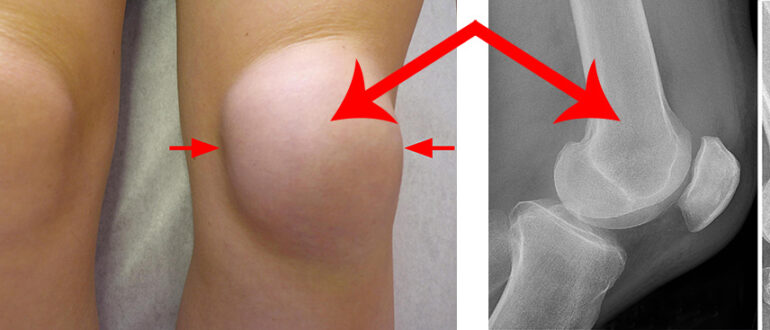

Симптомы растяжения мышц и сухожилий Растяжение сопровождается такими симптомами: нарастающий болевой синдром; нарушение двигательной активности поврежденной части тела; подкожное кровоизлияние; отек. Если у человека растяжение связок сухожилий, то…